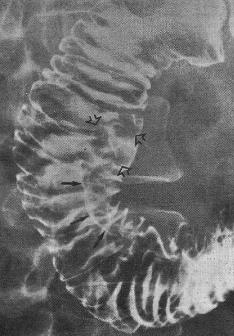

Les ulcere post bulbaire duodenale est le plus souvent

situe a D1 , D2 au niveau sus-valterien et a bord interne .Endoscopie

a cette portion est difficile . Image TOGD baryte

montre une stenose asymetrique avec image de ulcere au

millieure , aspect de "perle enfilee" .

Ulcere a bord interieure de

D2 au niveau sus-valerien . Image stenosant de

D2 avec niche remplisage de baryte . |

Ulcere stenosant de D2

aspect de " perle filee " avec image d'

epaississement des plies muqueuses duodenum en amont

et au aval ( duodenite ) . |